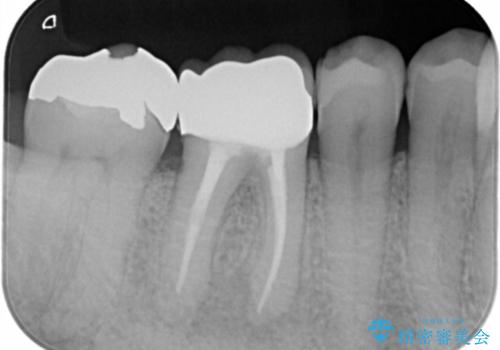

保険材料をセラミックにやり変えたい セラミックインレー

- 保険で治療された右下5番をセラミックにやり変え希望の患者様です。

切削量などを考慮し、セラミックインレーでの治療を選択しました。

古い材料と虫歯を全て除去した上で形成・印象を行い、セラミックインレーを装着しています。